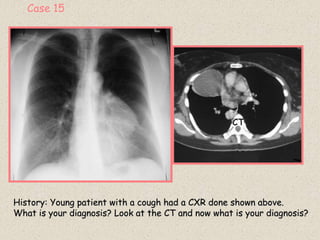

Case 15

History: Young patient with a cough had a CXR done shown above.

What is your diagnosis? Look at the CT and now what is your diagnosis?

CT

 Majority of thymic tumors are solid lymphoepithelial neoplasms (some are cystic)

 Occasionally they are fat-filled and referred to as thymolipomas (2-9% of thymomas).

 Thymomas are the most common anterior mediastinal neoplasms (1/3 are malignant)

 They can occur at any age but are rare in children.

 Arise from both epithelial and thymocytic elements of the thymic parenchyma.

 Virtually impossible to determine if they are benign or malignant from histology.

 More pertinent to prognosis from gross characteristics of local invasion or complete

encapsulation.

Clinical Symptoms:

 Close relationship between thymic tumors and myasthenia gravis.

 In the absence of myasthenia gravis most patients are asymptomatic.

 Distant metastases are rare.

 Recurrence rate following resection is high.

 Following resection, 50% of myasthenia gravis patients show some improvement.

Radiologic Findings:

 Most are seen near the junction of the heart and great vessels.

 They are round or oval and the margins are smooth or lobulated.

 May protrude to one or both sides of the mediastinum and often displace the heart and great

vessels posteriorly.

 It may be solid or cystic.

 Calcification may be visualized at the periphery of the lesion or throughout its substance.

 Because thymolipomas tend to grow large in size and are soft and pliable, they tend to slump

towards the diaphragm which may leave the superior mediastinum clear.

THYMIC TUMORS